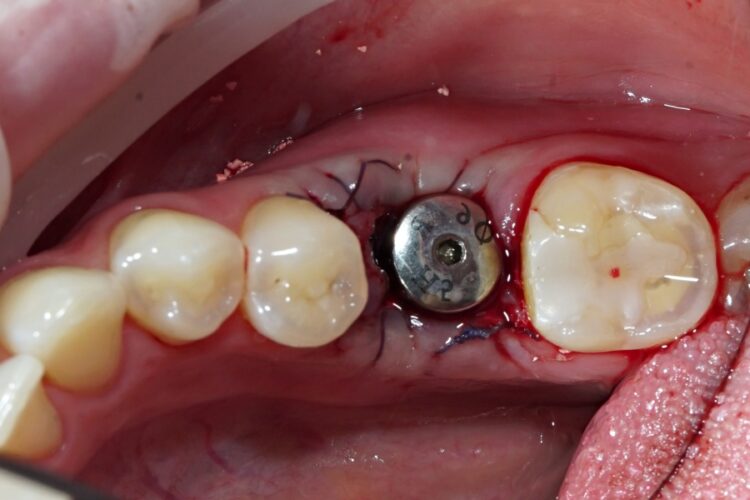

Проведення операції одномоментної імплантації: відразу після видалення коренів зруйнованого зуба було встановлено імплант із  формувачем ясен.

Під місцевим знеболюванням було видалено корені зуба атравматичним методом із максимальним збереженням кістки. Потім ми встановили імплант та формувач ясен. Ясна були вшиті максимально щільно навколо формувача.

Таким чином ми заощадили час і витрати пацієнта: не буде потреби у повторному візиті для встановлення формувача ясен, крім того – зникла необхідність проведення пластики ясен у подальшому.